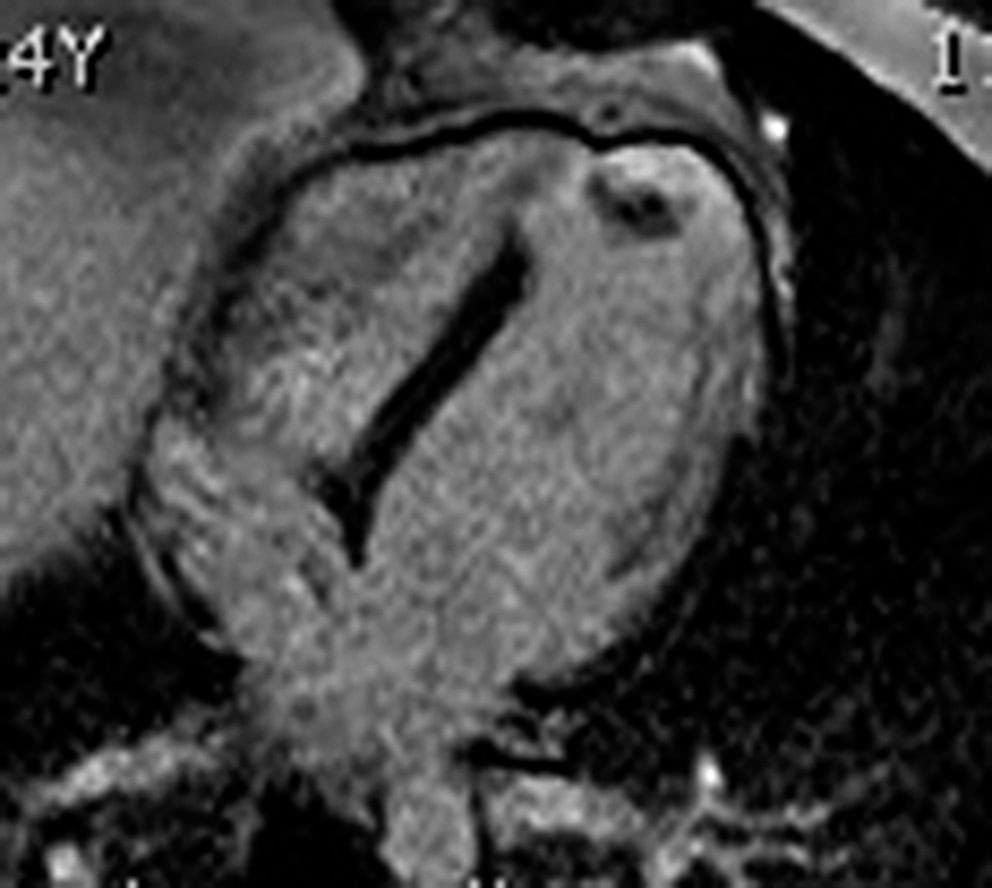

CARDIOLOGIE PÉDIATRIQUE 📌 À LA UNE : Cardiac evaluation of paediatric athletes: A clinical [...]